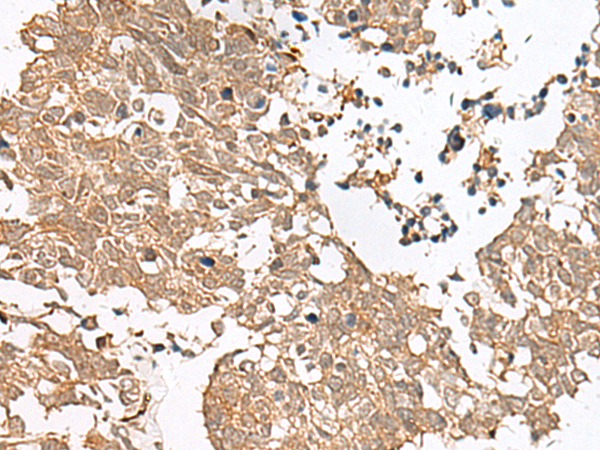

分类: 科研抗体货号: P13478别名: GPCR; PGR7; GALR4; GALRL; GPCR-2037应用: IHC反应种属: Human